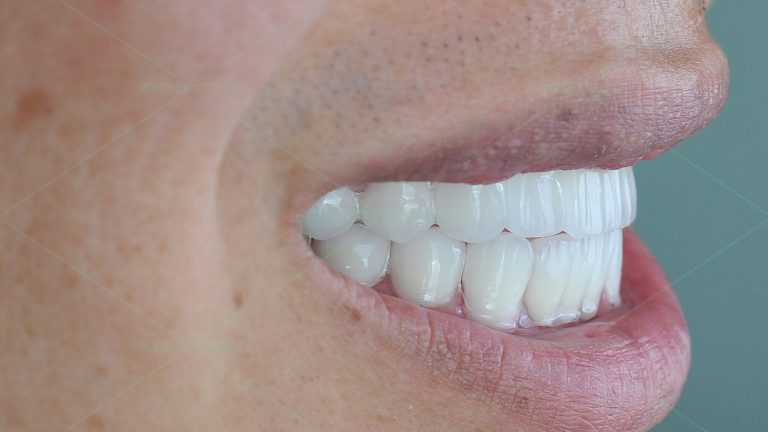

Bạn nữ 29 tuổi làm chủ 1 nhãn hàng thời trang và thường xuyên phải thuyết trình giới thiệu sản phẩm, vì vậy ngoại hình rất quan trọng với bạn, nhất là nụ cười. Đây cũng là 1 ca được tư vấn chỉnh nha trước rồi làm răng sứ, cũng như những nguy cơ khi […]